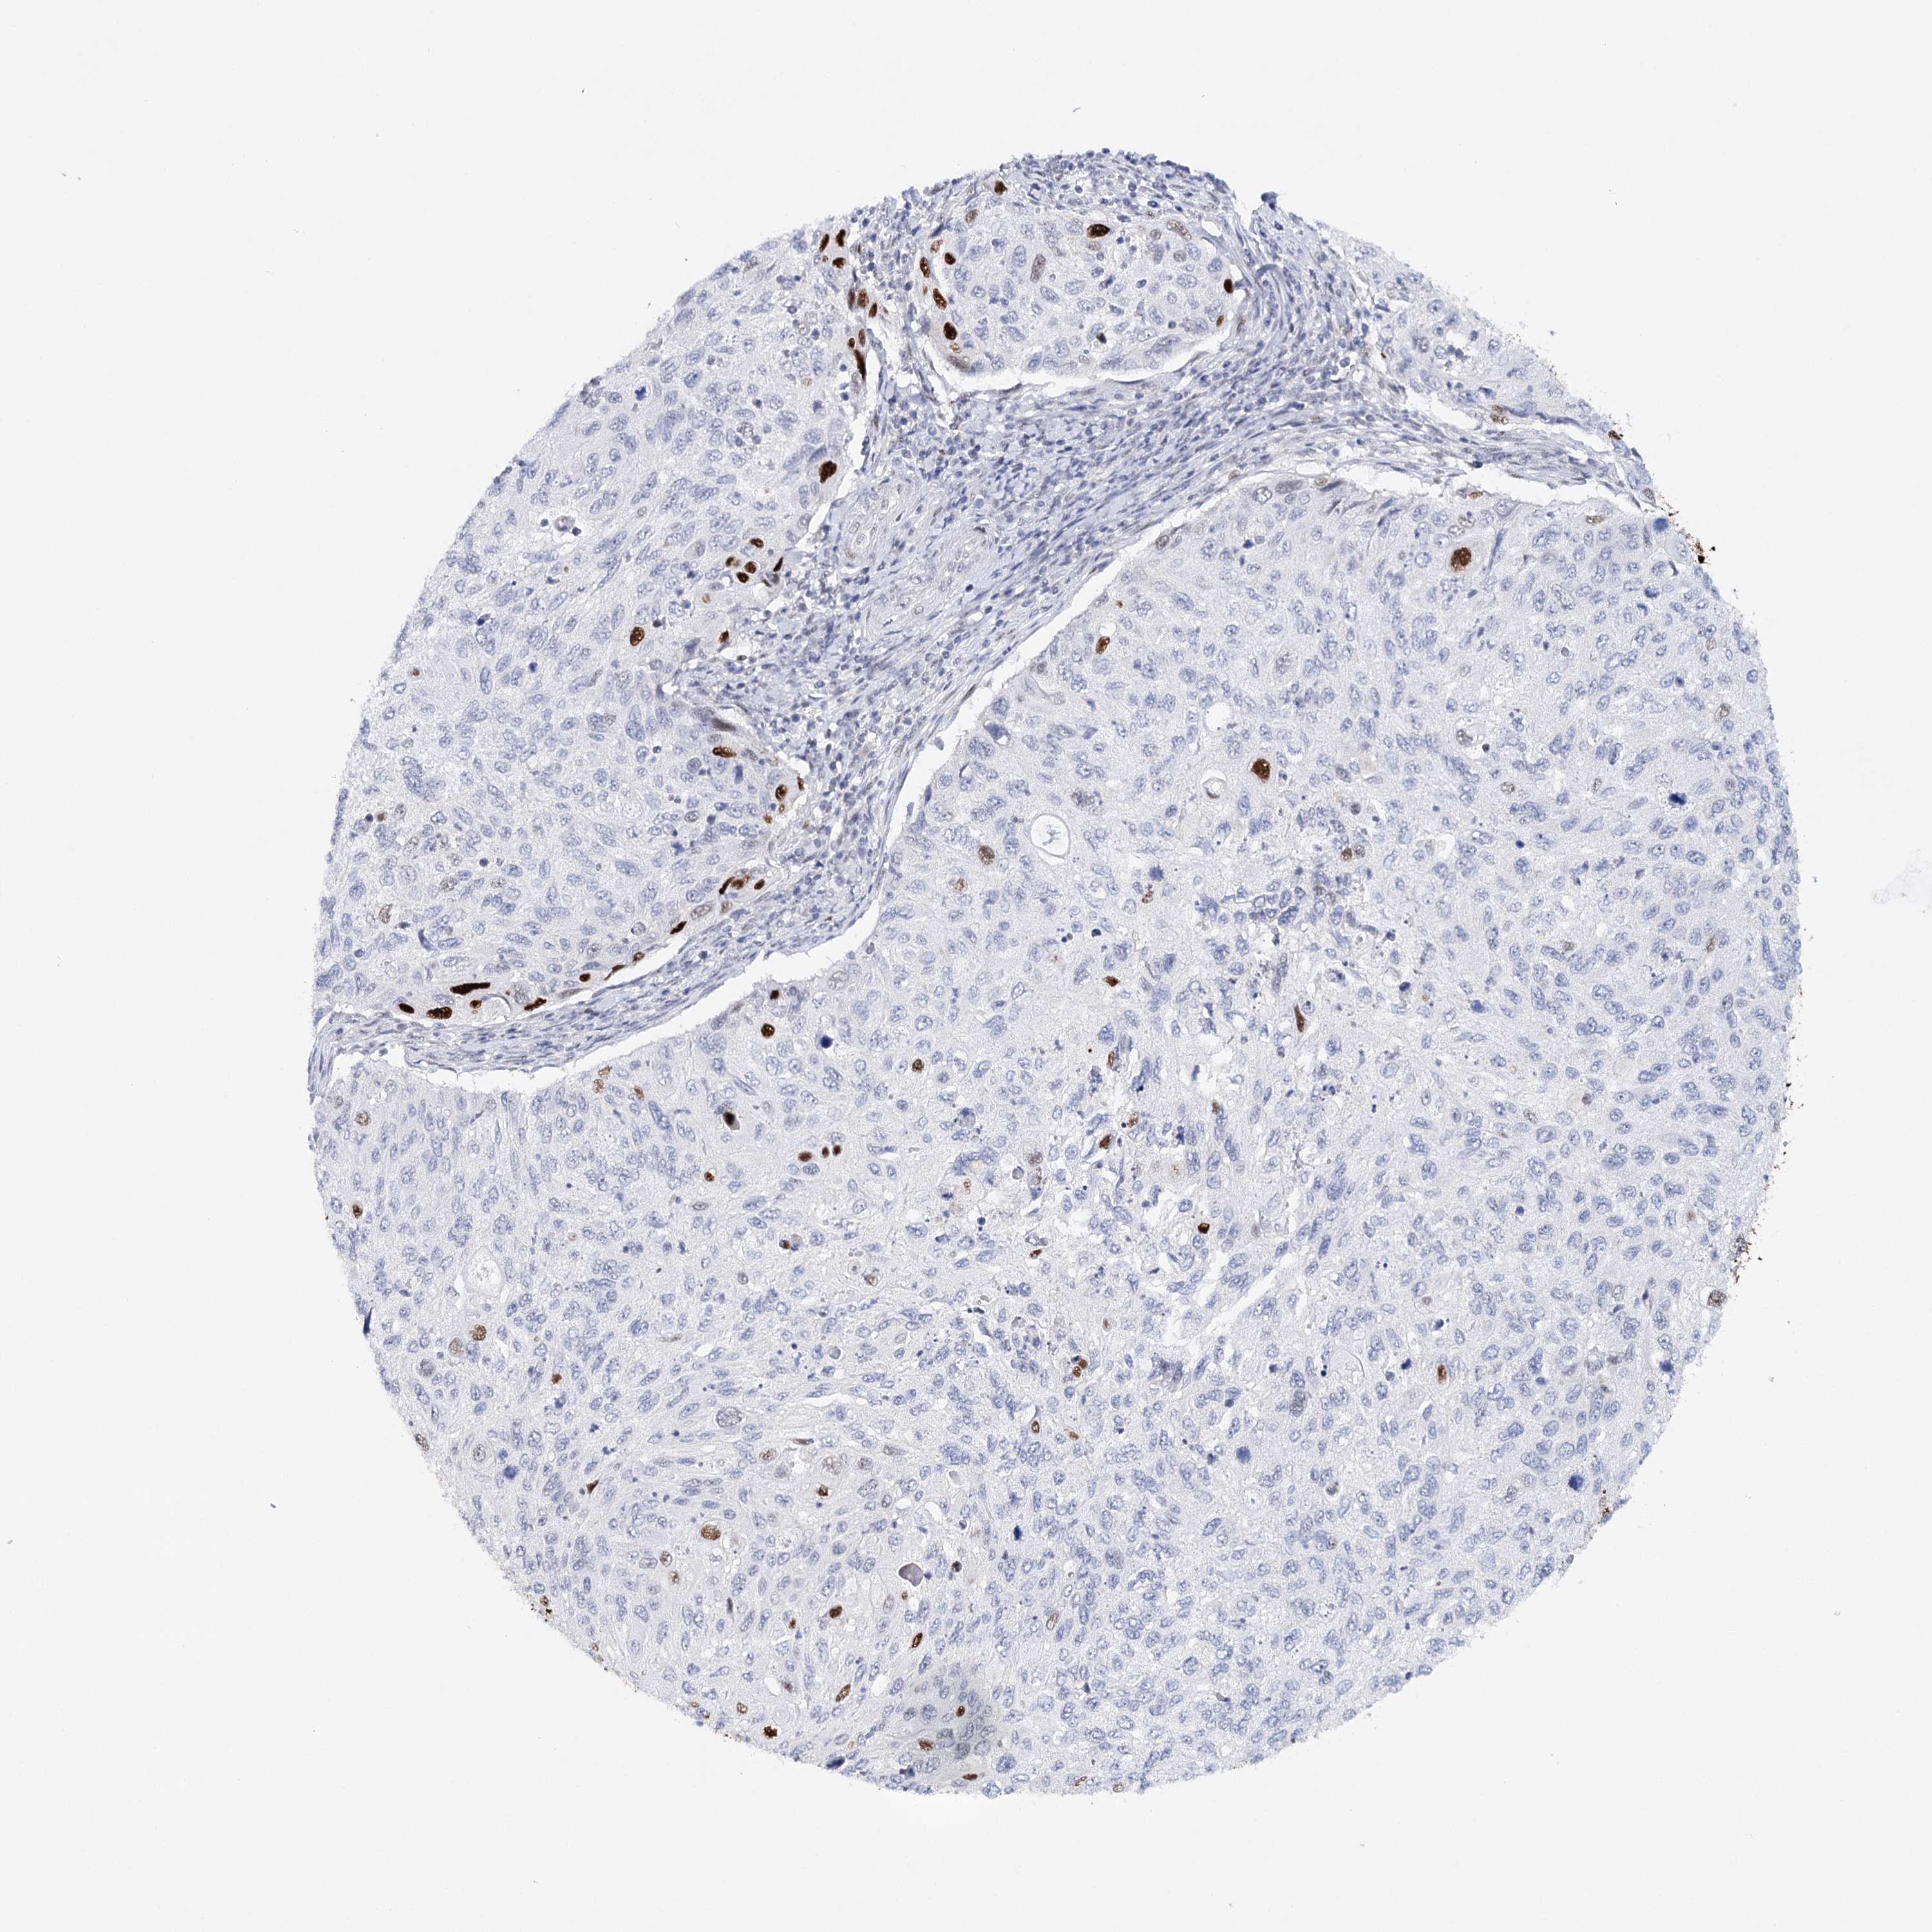

CERVICAL CANCER - Protein expressioni

A mouse-over function shows sample information and annotation data. Click on an image to view it in a full screen mode. Samples can be filtered based on level of antibody staining by selecting one or several of the following categories: high, medium, low and not detected. The assay and annotation is described here.

Note that samples used for immunohistochemistry by the Human Protein Atlas do not correspond to samples in the TCGA dataset.

Antibody stainingi

Antibody staining in the annotated cell types in the current human tissue is reported as not detected, low, medium, or high, based on conventional immunohistochemistry profiling in selected tissues. This score is based on the combination of the staining intensity and fraction of stained cells.

Each image is clickable and will lead to virtual microscopy that enables deeper exploration of all samples and also displays staining intensity scores, fraction scores and subcellular localization as well as patient and tissue information for each sample.

Antibody CAB072876

Squamous cell carcinoma, NOS